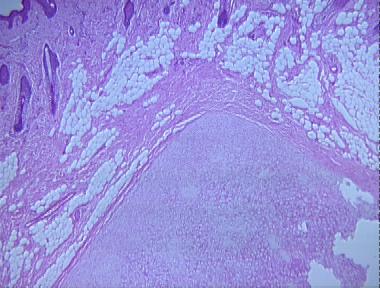

cutaneous chondroma

Histologic Features